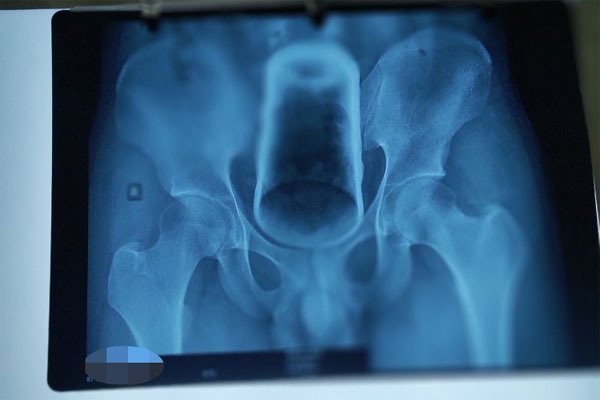

Chiếc ly thủy tinh trong hậu môn thanh niên 21 tuổi ở Tiền Giang. Ảnh: BVCC